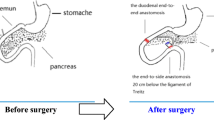

All animals were anesthetized by inhalation of sevoflurane. The two procedures used are similar to those previously reported [1, 11], and a diagram of these procedures is shown in Fig. 1. [Reviewer 2, comment 2]

A schematic diagram of new biliopancreatic diversion and duodenal bypass surgeries. a New biliopancreatic diversion. End-to-end duodenoduodenostomy at 0.5 cm proximal to and 0.5 cm distal to the major duodenal papilla, followed by transfer of the intestinal segment containing the major duodenal papilla to the proximal jejunum (20 cm from the ligament of Treitz) [11]. b Duodenal-jejunal bypass. The duodenum was separated from the stomach, and bowel continuity was interrupted at the level of the distal jejunum, (10 cm from the ligament of Treitz). The distal of the two limbs was directly connected to the stomach (gastrojejunal anastomosis) and the proximal limb carrying the biliopancreatic to the alimentary limb at a distance of 10 cm from the gastrojejunal anastomosis (Roux-en-Y reconstruction) [1]

In this group, a segment including the bilioenteric confluence (containing the biliopancreatic duct), duodenum, and proximal jejunum was incised and reattached to the distal jejunum. To obtain this segment, the duodenum was cut 0.5 cm below the pylorus, the jejunum was cut at 10 cm distal to the ligament of Treitz, and the duodenal end of the segment was closed. The remaining end of the jejunum was anastomosed with the remaining end of the duodenum (end-to-end anastomosis), and the jejunal end of the duodenal-jejunal segment was reconnected with the remaining jejunum by end-to-side anastomosis at 20 cm distal to the ligament of Treitz (Fig. 1b). The operation time was 45 ± 5 min.

NBPD group

In this group, only the bilioenteric confluence was incised from the duodenum and attached to the distal jejunum. The segment of the duodenum containing the biliopancreatic confluence was incised by transections made 0.5 cm proximal to and 0.5 cm distal to the this confluence. The proximal end of the segment was closed, and the proximal and distal ends of the remaining duodenum anastomosed end-to-end. The incised [Reviewer 2, comment 1] duodenal segment containing the bilioenteric confluence was anastomosed with the jejunum 20 cm distal to the ligament of Treitz (end-to-side anastomosis) (Fig. 1a). The operation time was 40 ± 5 min.